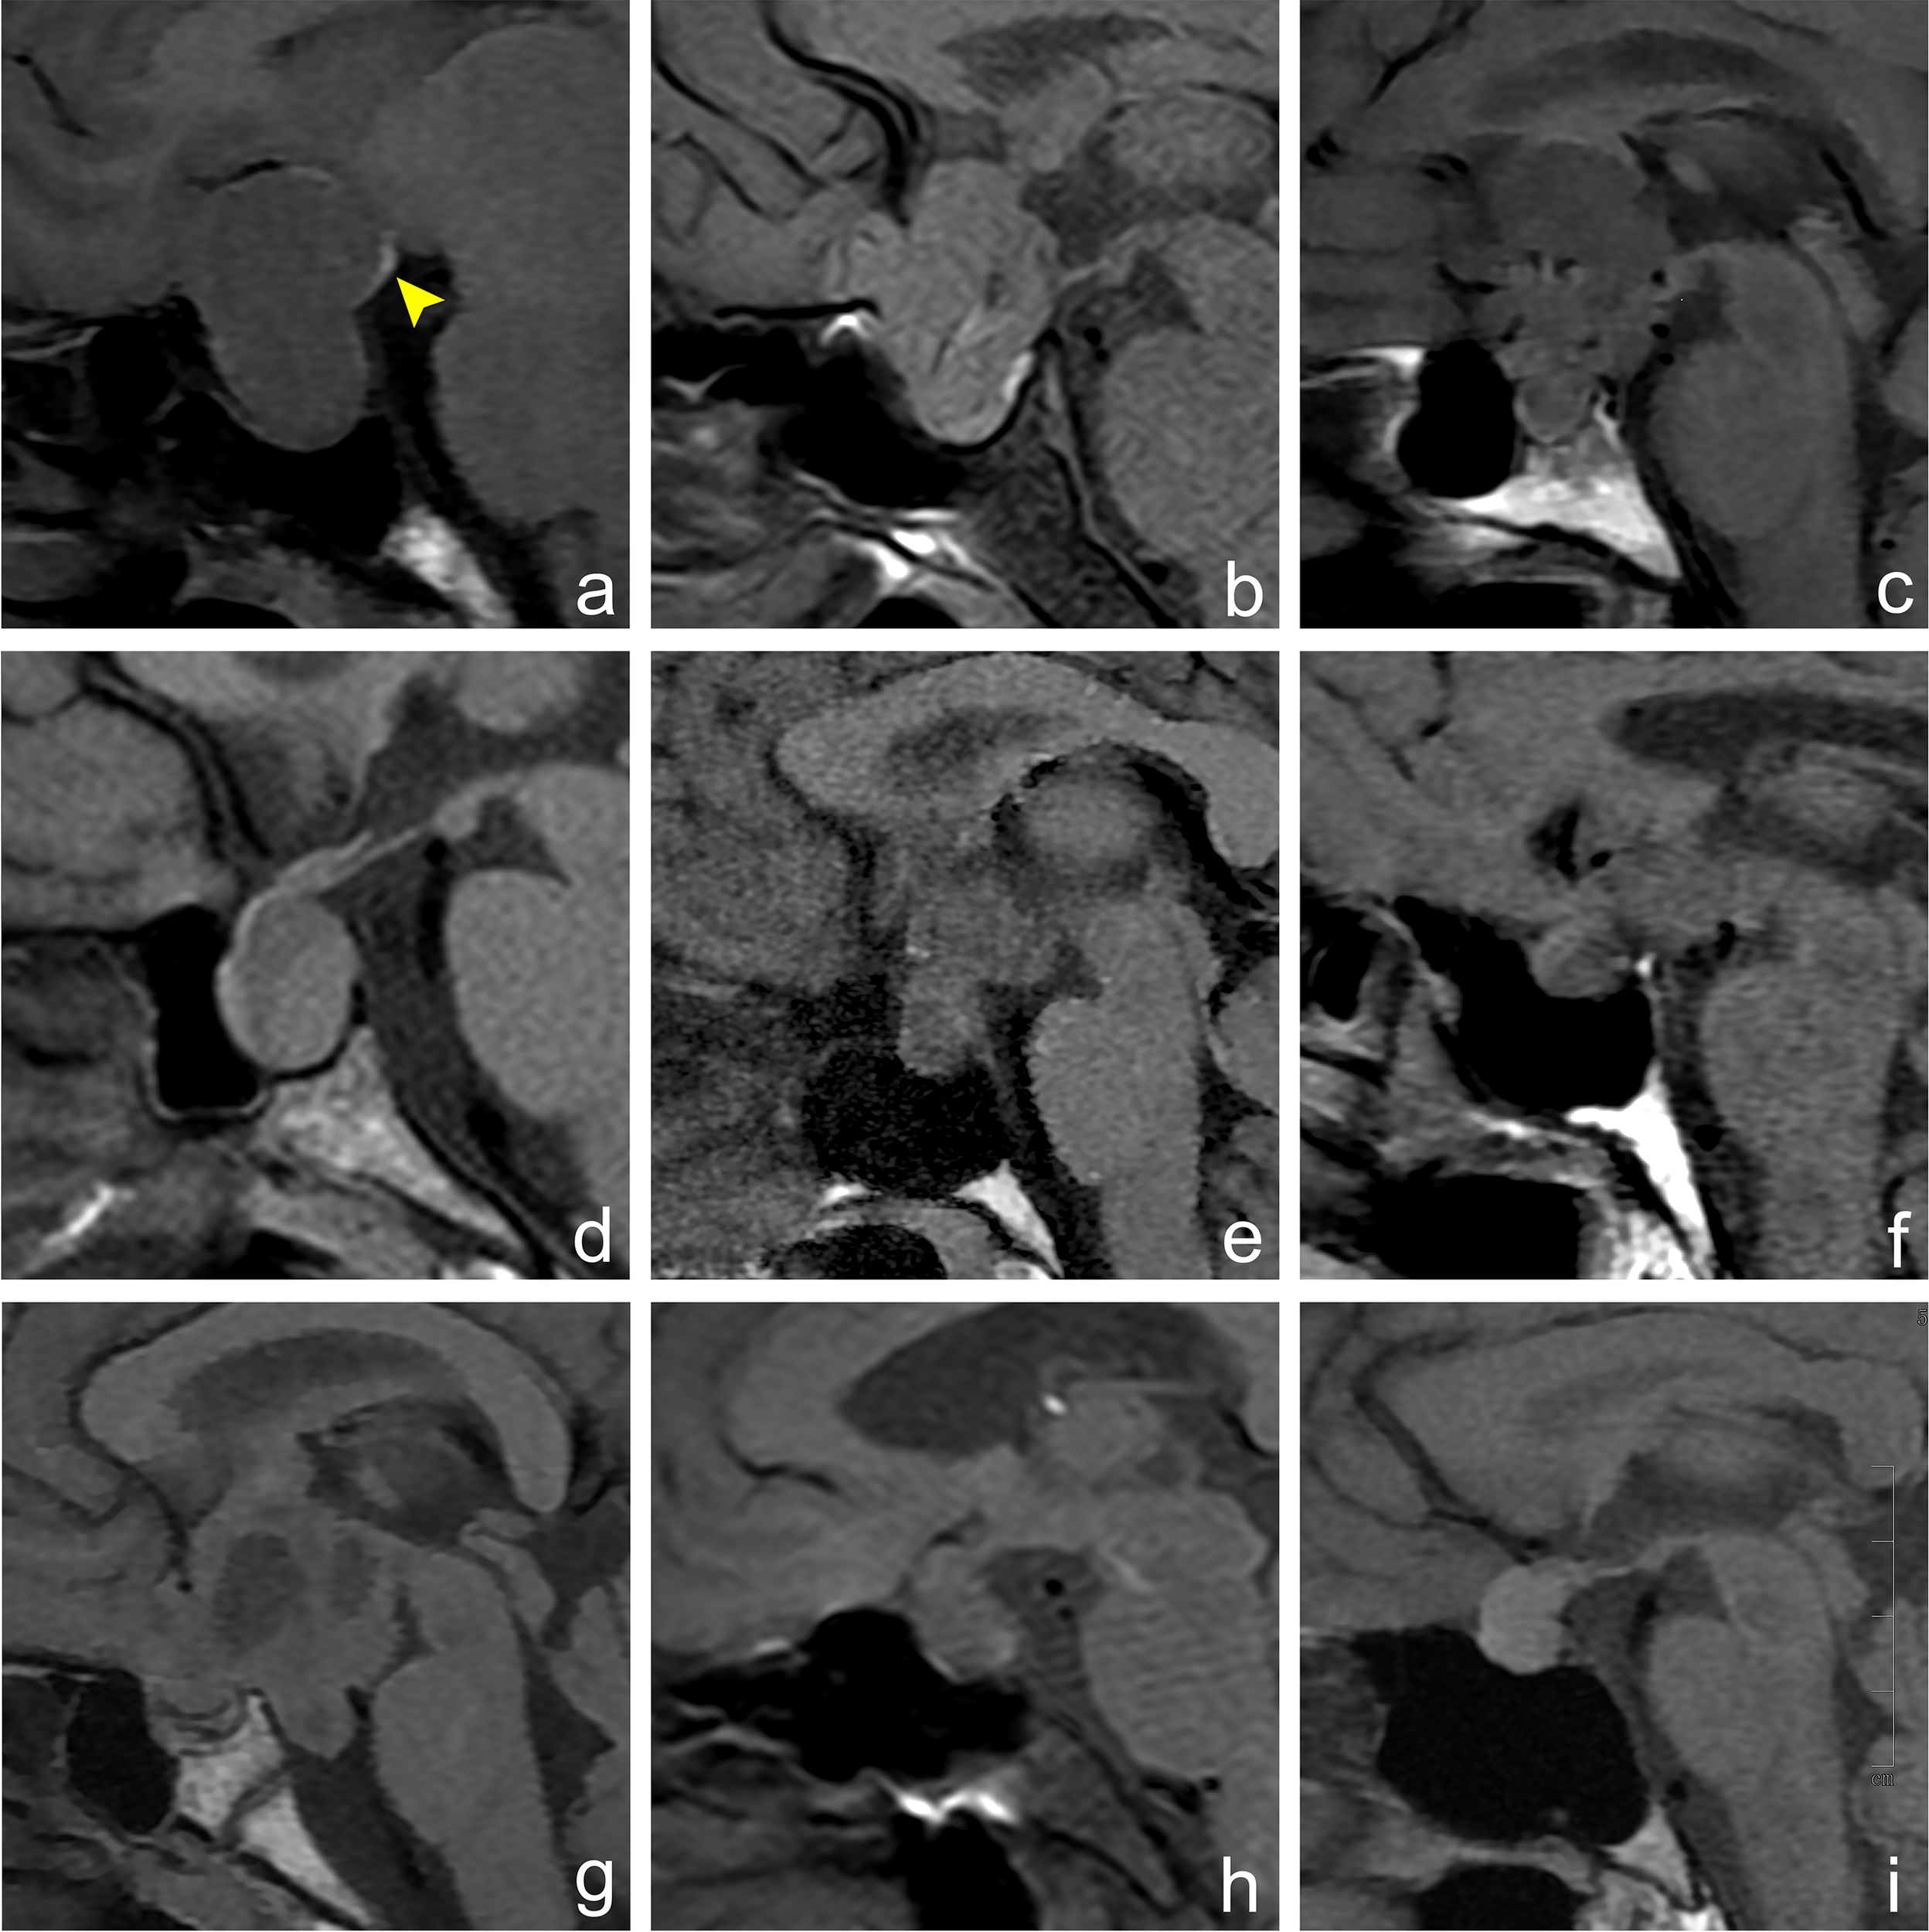

Figure 2

Imaging manifestations of hyperintense signal in posterior pituitary in different sellar diseases. Figures (A–I) show an MRI sagittal T1WI non-enhanced scan of different lesions in the sellar region. (A) A 30-year-old female, pituitary macroadenoma, ectopic hyperintense signal in the posterior pituitary, which is located at the posterior upper edge of the tumor (arrowhead). (B) A 64-year-old male, meningioma, normal hyperintense signal in the posterior pituitary, which is located behind the intrasellar adenohypophysis. (C) A 39-year-old male, craniopharyngioma, hyperintense signal in the posterior pituitary disappears. (D) A 54-year-old female, Rathke cleft cyst, hyperintense signal in the posterior pituitary disappears. (E) A 35-year-old female, germ cell tumor, hyperintense signal in the posterior pituitary disappears. (F) A 60-year-old male, metastatic tumor, hyperintense signal in the posterior pituitary disappears. (G) A 14-year-old female, glioma, hyperintense signal in the posterior pituitary disappears. (H) A 56-year-old female, cryptococcal granuloma of pituitary, hyperintense signal in the posterior pituitary disappears. (I) A 40-year-old female, abscess of the pituitary, hyperintense signal in the posterior pituitary disappears.